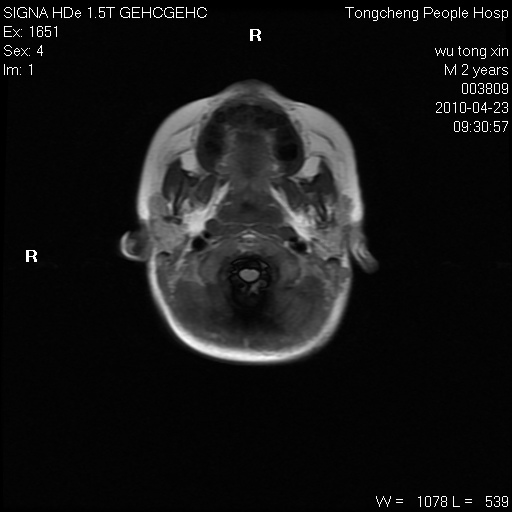

以下是引用赵物学在2010-4-25 12:43:00的发言:[br]巨脑回[br]侧脑室后角低密度影考虑hie或肾上腺脑白质营养不良?[br][br][本贴已被 赵物学 于 2010-4-25 12:51:28 修改过]

以下是引用gaoxiao在2010-4-25 16:54:00的发言:[br]巨脑回畸形。脑白质髓鞘化不良

以下是引用pujunzhi在2010-4-25 21:35:00的发言:[br]考虑 1双侧大脑皮质发育不良 2轻度脑积水 3双侧脑室后角旁片状长t1长t2信号,需继续观察,因为正常小儿此处脑白质的髓鞘化时间可以延迟到4-6岁,才显示正常。